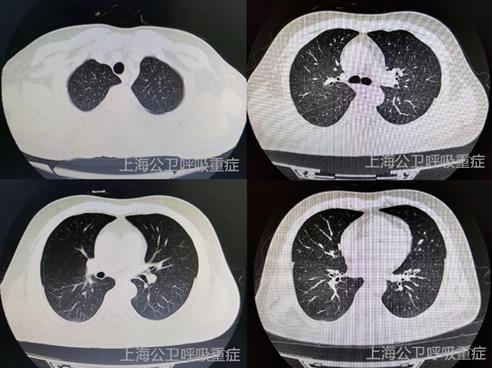

吸入性肺炎ct影像图

吸入性肺炎 (co中毒后误吸致右侧肺炎)

吸入性肺炎影像学表现